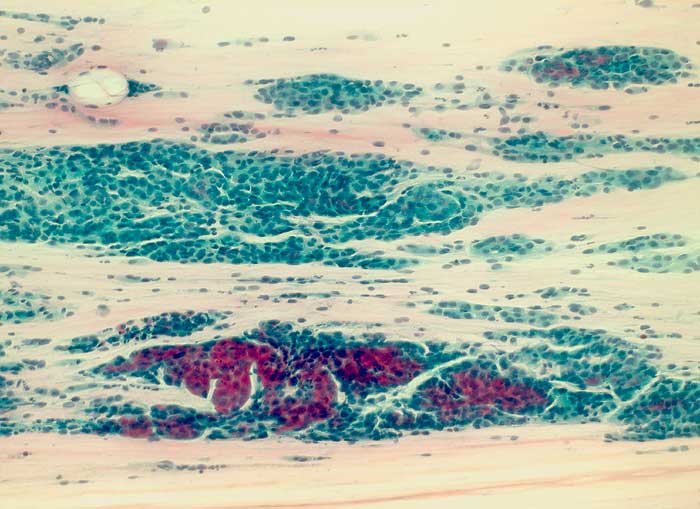

seröses papilläres Adenokarzinom des Endometrium

Portioabstrich: Der Ausstrich enthält auffallend viele Zellen mit zum teils tapetenförmigen, teils auch angedeutet papilliformen Verbänden. Die Zellen sind etwas grösser als Basalzellen des Plattenepithels und besitzen deutliche polymorphe Kerne. Zytoplasmaleib uncharakteristisch zyanophil.

Histologie: serös papilläres Endometriumkarzinom

Zytologische Diagnose: Massenhaft Verbände von Epithelien mit Kernatypien.

Im vorliegenden Befund lässt sich nicht sicher entscheiden, ob die Zellen aus der Portio oder aber aus dem Endometrium stammen. Histologische Abklärung ratsam.